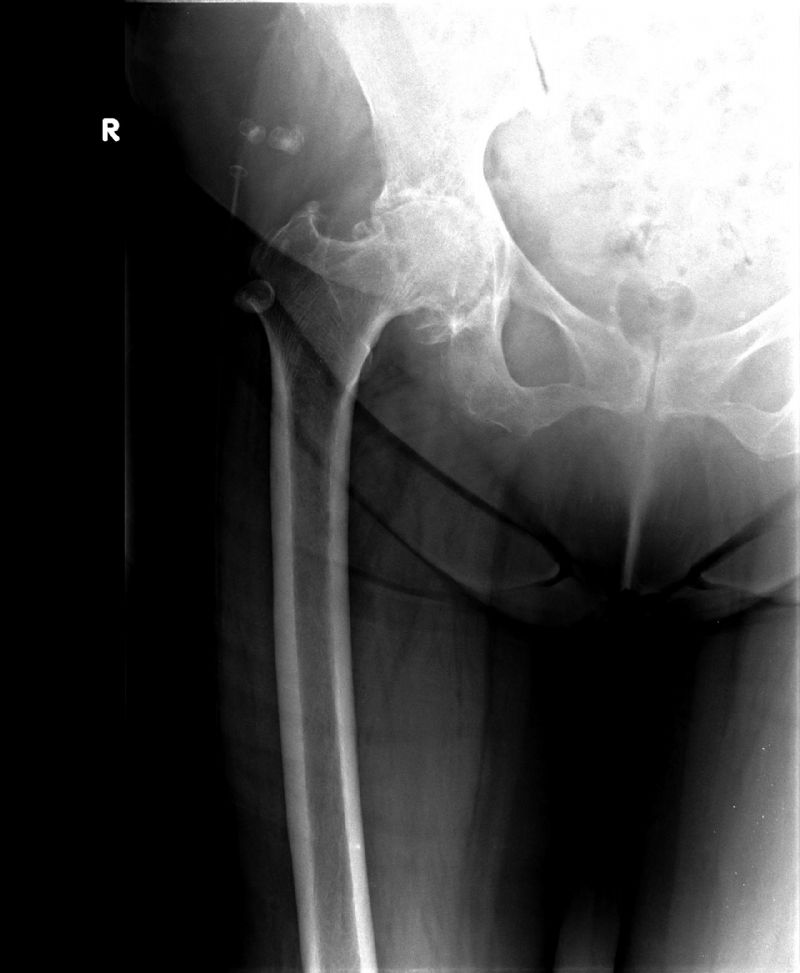

Total Kalça Protezi Örnek Olgular